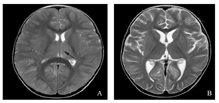

A.2020年10月5日头颅MRI示T2WI背侧丘脑饱满,信号偏高;B.2020年10月13日头颅MRI示T2WI背侧丘脑异常信号已不明显。

病例2,患儿,男,1岁2个月。因"发热5 d,反复抽搐2次"于2020年10月4日入院。入院查体:T 37 ℃,P 140次/min,R 32次/min,BP 110/90 mmHg,GCS评分9分,双眼凝视,反应差,面色苍白,全身浅表淋巴结未触及肿大,瞳孔等大等圆,直径2 mm,对光反射迟钝,颈软,无抵抗,双肺听诊呼吸音粗,未闻及干湿性啰音,心音中,律齐,心前区未闻及病理性杂音,腹软,未触及包块,肝脾肋下未触及,肢端凉,毛细血管再充盈时间3 s,双侧巴氏征阴性,肌力及肌张力正常。入院后行腰椎穿刺术,脑脊液常规:白细胞2.0×106/L,脑脊液生化:微量总蛋白3 513.3 mg/L,脑脊液病原体高通量测序:HHV-6B。10月5日头颅MRI平扫示:双侧大脑半球皮层及双侧基底节区、背侧丘脑广泛异常信号(图2A)。血尿遗传代谢病筛查阴性。结合患儿HHV-6B感染后出现发热、抽搐、意识障碍等急性脑病症状,脑脊液无细胞数升高、脑脊液蛋白水平升高及以上头颅影像结果,诊断急性坏死性脑病,予更昔洛韦抗病毒,力月西联合德巴金持续泵注止痉,甲泼尼龙大剂量冲击20 mg/(kg·d),连用3 d,人免疫球蛋白1 g/(kg·d),连用2 d。10月13日复查头颅MRI示:双侧丘脑异常信号已不明显,双侧大脑半球皮层及双侧基底节区病变较10月5日MRI明显改善(图2B)。患儿于入院第4天意识转清,未再抽搐,未遗留神经系统后遗症,于入院第11天康复出院。